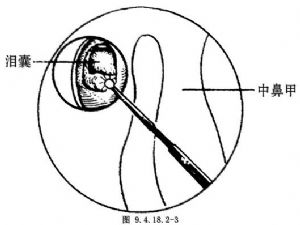

3.用电钻或骨凿去除泪囊投影区上颌骨额窦、泪骨的部分骨质,开一直径1cm的骨窗以显露泪囊壁(图9.4.18.2-3)。

4.经泪小点插入泪道探子至泪囊,活动探子并于内镜下观察骨窗外是否为泪囊。